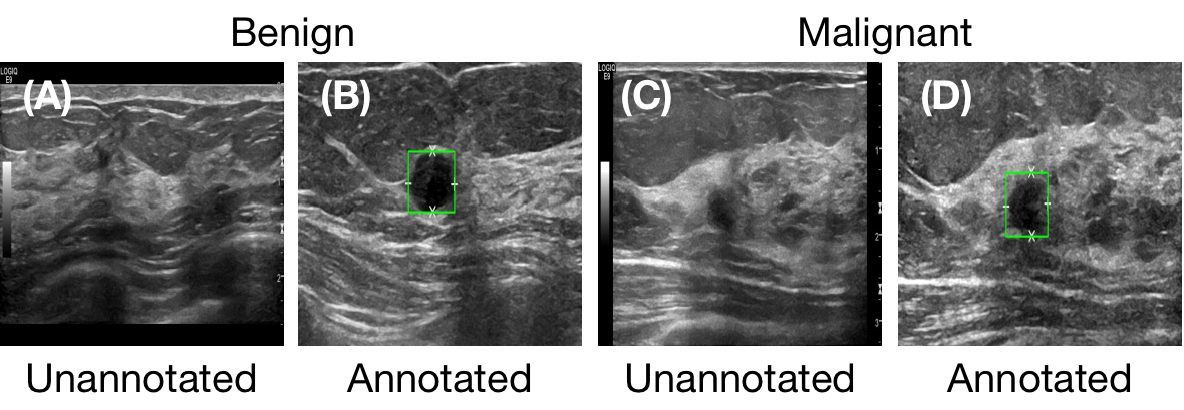

The proposed method was evaluated on two breast ultrasound image datasets. The first dataset is a public dataset, the Breast Ultrasound Dataset (BUD) [33]. This database includes a total of 780 images with image size of pixels after scanning 600 female patients acquired by LOGIQ E9 ultrasound system and LOGIQ E9 Agile ultrasound system. This dataset was fully-annotated with segmentation masks as the lesion localization labels. The details of this dataset are shown in the table 1, and several example images are shown in Figure 3.

The second dataset includes breast tumor ultrasound images collected at Mayo Clinic (MBUD). A total of 160 scanning videos with image size of pixels were collected after scanning 136 patients with LOGIQ E9 ultrasound system. A total of 22202 images were extracted from these videos and annotated with class labels. Within them, there were 384 images manually annotated with bounding boxes as the lesion localization labels. Several example images are shown in Figure 4. We named the dataset with whole images but partial location annotations as P-MBUD, and the sub-dataset with 384 fully-annotated images as the F-MBUD. The details of the F-MBUD and P-MBUD datasets are shown in Table 2. Particularly, P-MBUD was used as the incomplete dataset to evaluate the performance of our proposed semi-supervised learning strategy.